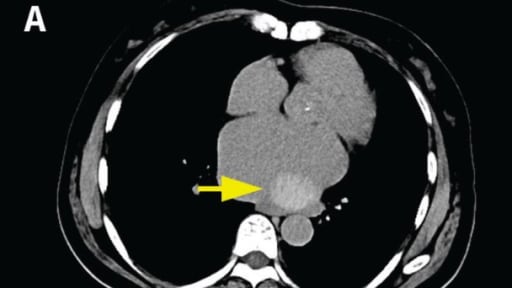

Pneumologie

Auf dieser Seite erwartet Sie Wissenswertes und Praxisrelevantes aus der Lungenheilkunde – von neuen Studiendaten über aktuelle Leitlinien und Kongressberichte bis hin zu spannenden Fällen aus der Praxis.